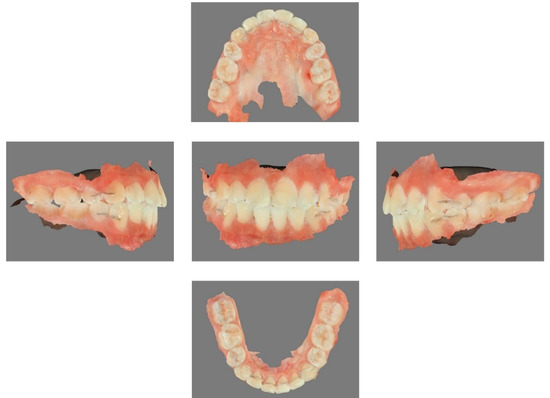

2.4. The Manufacturing Process of Clear Aligners by CAD/CAM